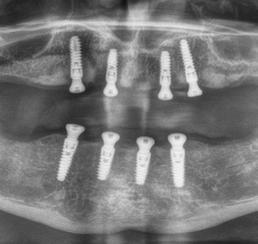

Az 50 éves nőpáciens az alsó és felső állcsont területén egyaránt panaszt (fájdalom, ráharapási érzékenység) okozó, harmadfokban mozgatható fogak miatt jelentkezett rendelőnkben. Az általános anamnézisben említést érdemlő betegség, műtét nem szerepelt. Az elvégzett klinikai és radiológiai vizsgálatok (1–2. ábra) alapján fogai reménytelen parodontális státusúnak bizonyultak, hosszú távon sem megtartásuk, sem protetikai célú felhasználásuk nem volt lehetséges. A parodontális prognózis a fogak eltávolításának abszolút indikációját jelentette. Ezáltal mindkét állcsontban teljes foghiány kialakulásával kellett számolnunk. A protetikai szemléletű, „visszafelé” tervezés elveit követtük a hosszú távú funkcionális, esztétikai siker és szöveti stabilitás elérése érdekében: mindkét állcsontban overdenture típusú fogpótlás készítése mellett döntöttünk. A megfelelő implant-protetikai rehabilitáció alapja az implantátumok megfelelő pozicionálása. A korábbi parodontális kórfolyamat következtében a processus alveolarisokat érintő eredendő csontdeficittel kellett számolnunk, amelyet tovább súlyosbíthatott volna a hagyományos extrakciós technikát követő involúciós atrófia. Ezért a páciens kivizsgálása és megfelelő előkészítése után a fog eltávolításával egy időben PRF

27 VI. ÉVFOLYAM – 2023. 4. SZÁM

Sticky Tooth segítségével kivitelezett alveolus prezerváció mellett döntöttünk, a megfelelő csontos és mukogingivális gyógyulás minőségi és mennyiségi elősegítése érdekében. A PRF készítmény mennyiségét, minőségét, kezelhetőségét és hatékonyságát jelentősen befolyásolják a páciens laborértékei, ezért kezelési protokollunk szerint a műtétet megelőzően minden esetben laborvizsgálatot végzünk (hemoglobin: 134 g/liter, hematokrit: 0,43, fehérvérsejt: 6,6 G/liter, CRP: 13,60 mg/liter, vércukor: 6,2 mmol/liter, összkoleszterin: 7,00 mmol/liter, triglicerid: 1,08 mmol/liter, HDL koleszterin 2,57 mmol/liter, LDL koleszterin 1,12 mmol/liter), D3 vitamin: 117,5 nmol/liter).

A fogak eltávolítása és az alveoláris csont megőrzésének és regenerációjának segítése céljából elvégzett augmentáció altatásban történt. Óvatos, atraumatikus extrakciót követően eltávolítottuk a parodontális és periapikális gyulladásos folyamatok eredményeként jelen lévő sarjszövetet. A bukkális csontfal hiánya és a tervezett vertikális augmentáció miatt indokolt membrántechnika megfelelő kivitelezése céljából a felső állcsonton mukoperioszteális lebenyt képeztünk (3–4. ábra). Az alveolus prezervációt Sticky Tooth, PRF és titánerősítésű teflon (PTFE-Ti) membránok segítségével végeztük el, a J. Choukroun által megadott vérvételi és centrifugálási protokoll (28) elveinek betartásával: kizárólag Process for PRF Duo Quattro System eszközöket, centrifugát, vérvételi egységet és csöveket, a membránok előállításához PRF Boxot használtunk. Az A-PRF és S-PRF csöveket a PomPac eljárásnak megfelelően 4 Celsius-fokra előhűtöttük. Az eltávolított fogak makroszkópos tisztítását és darabolását nagy fordulattal (300 000 RPM) fogászati turbinába helyezett gyémántfúróval végeztük, majd Tooth Transformer™ berendezéssel, annak gyári reagens rendszerével kezelt őrleményt nyertünk. A Sticky Tooth készítmény előállítása a PRF készítmény és az őrlemény

60/40 arányú keverésével történt (5–7. ábra), A-PRF és A-PRF/S-PRF membránokat készítettünk (8. ábra). Az alveólusokat a grafttal feltöltöttük, a felső front régióban vertikális augmentációt végeztünk a tervezett alveoláris csontmagasság elérésének céljából (9–10. ábra). A vertikális augmentáció támogatására titán mikrocsavarokkal rögzített, titánerősítésű teflonmembránokat alkalmaztunk, amelyekre egy rétegben A-PRF membránokat, és egy rétegben A-PRF/S-PRF membránokat helyeztünk. Az alsó állcsont esetében vertikális augmentáció nem volt szükséges, célunk az alveoláris kemény- és lágyszöveti struktúrák prezervációja volt, a graftot csak PRF memb-

A gyógyulási időszakot követően a csontos gyógyulás ellenőrzése és az implantáció tervezése céljából állcsonti CT-felvételt készítettünk. A CT-felvételen tökéletes csontos gyógyulást észleltünk, az alveoláris csont volumene

teljes mértékben megtartott, a vertikális augmentáció a tervezettnek megfelelő eredményű volt (13–15. ábra), a klinikai kép is ennek megfelelően alakult, optimális menynyiségű keratinizált ínnyel és azt adekvát sebészi technika eredményeképpen megtartott vesztibulummal (16–17. ábra). Az alsó és felső állcsontba 4-4 darab Bredent COPA Sky implantátumot ültettük, D1-D2 csontminőség mellett,